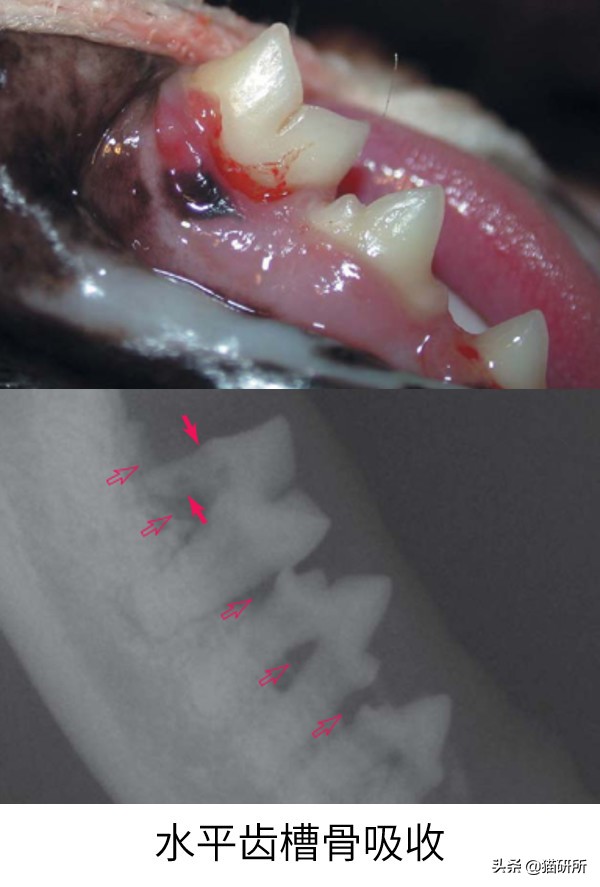

口腔X线检查

用于评估根尖、牙周病及提示肿瘤的骨吸收

2014年发表的一项对2002年到2012年的猫慢性口龈炎(FCGS)的X线结果的统计显示,患FCGS的猫,更容易出现:外部炎性齿根吸收、根尖滞留、齿槽骨吸收(特别是水平骨)。

图自DeBowes L J, DuPont G A